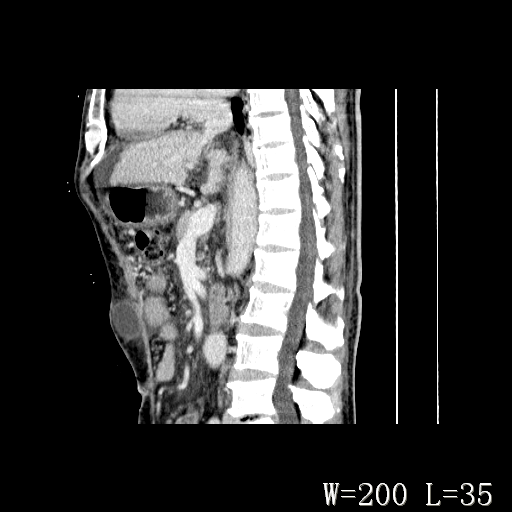

男,52岁,门脉高压断流术后1年,发现腹部肿物2月。

1)前腹壁中线区(脐上方)囊性占位性病变,考虑淋巴囊肿。2)腹水。